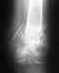

Re: Открытый перелом голени(посередине) с осколком и смещением

Величина нагрузки зависит от: срока сращения, условий регенерации (степень повреждения мягких тканей в области перелома, сопутствующих заболеваний, индивидуальных особенностей регенерации организма, вида остеосинтеза и т.д.), выраженности костной мозоли.